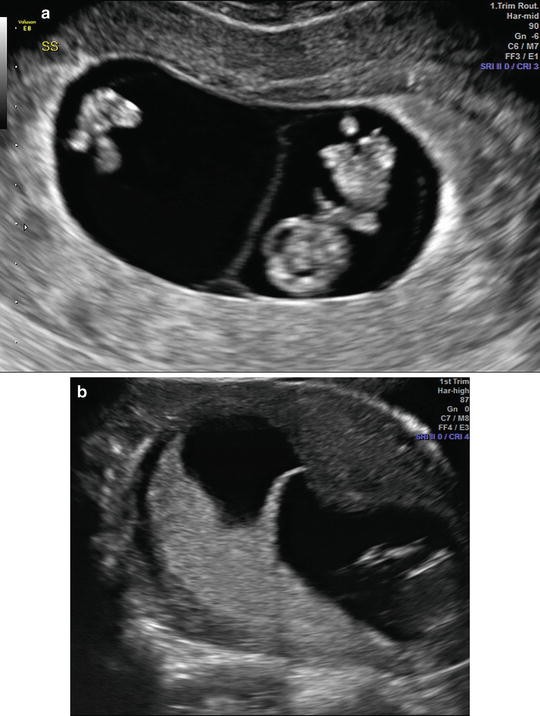

ISUOG Guidelines 249 Lambda sign T sign Figure 1 Ultrasound images in the ο¬rst trimester of: (a) a dichorionic diamniotic twin pregnancy, in which the twins are separated by a thick layer of fused chorionic membranes; (b) a monochorionic diamniotic twin pregnancy, in which the twins are separated by only two thin